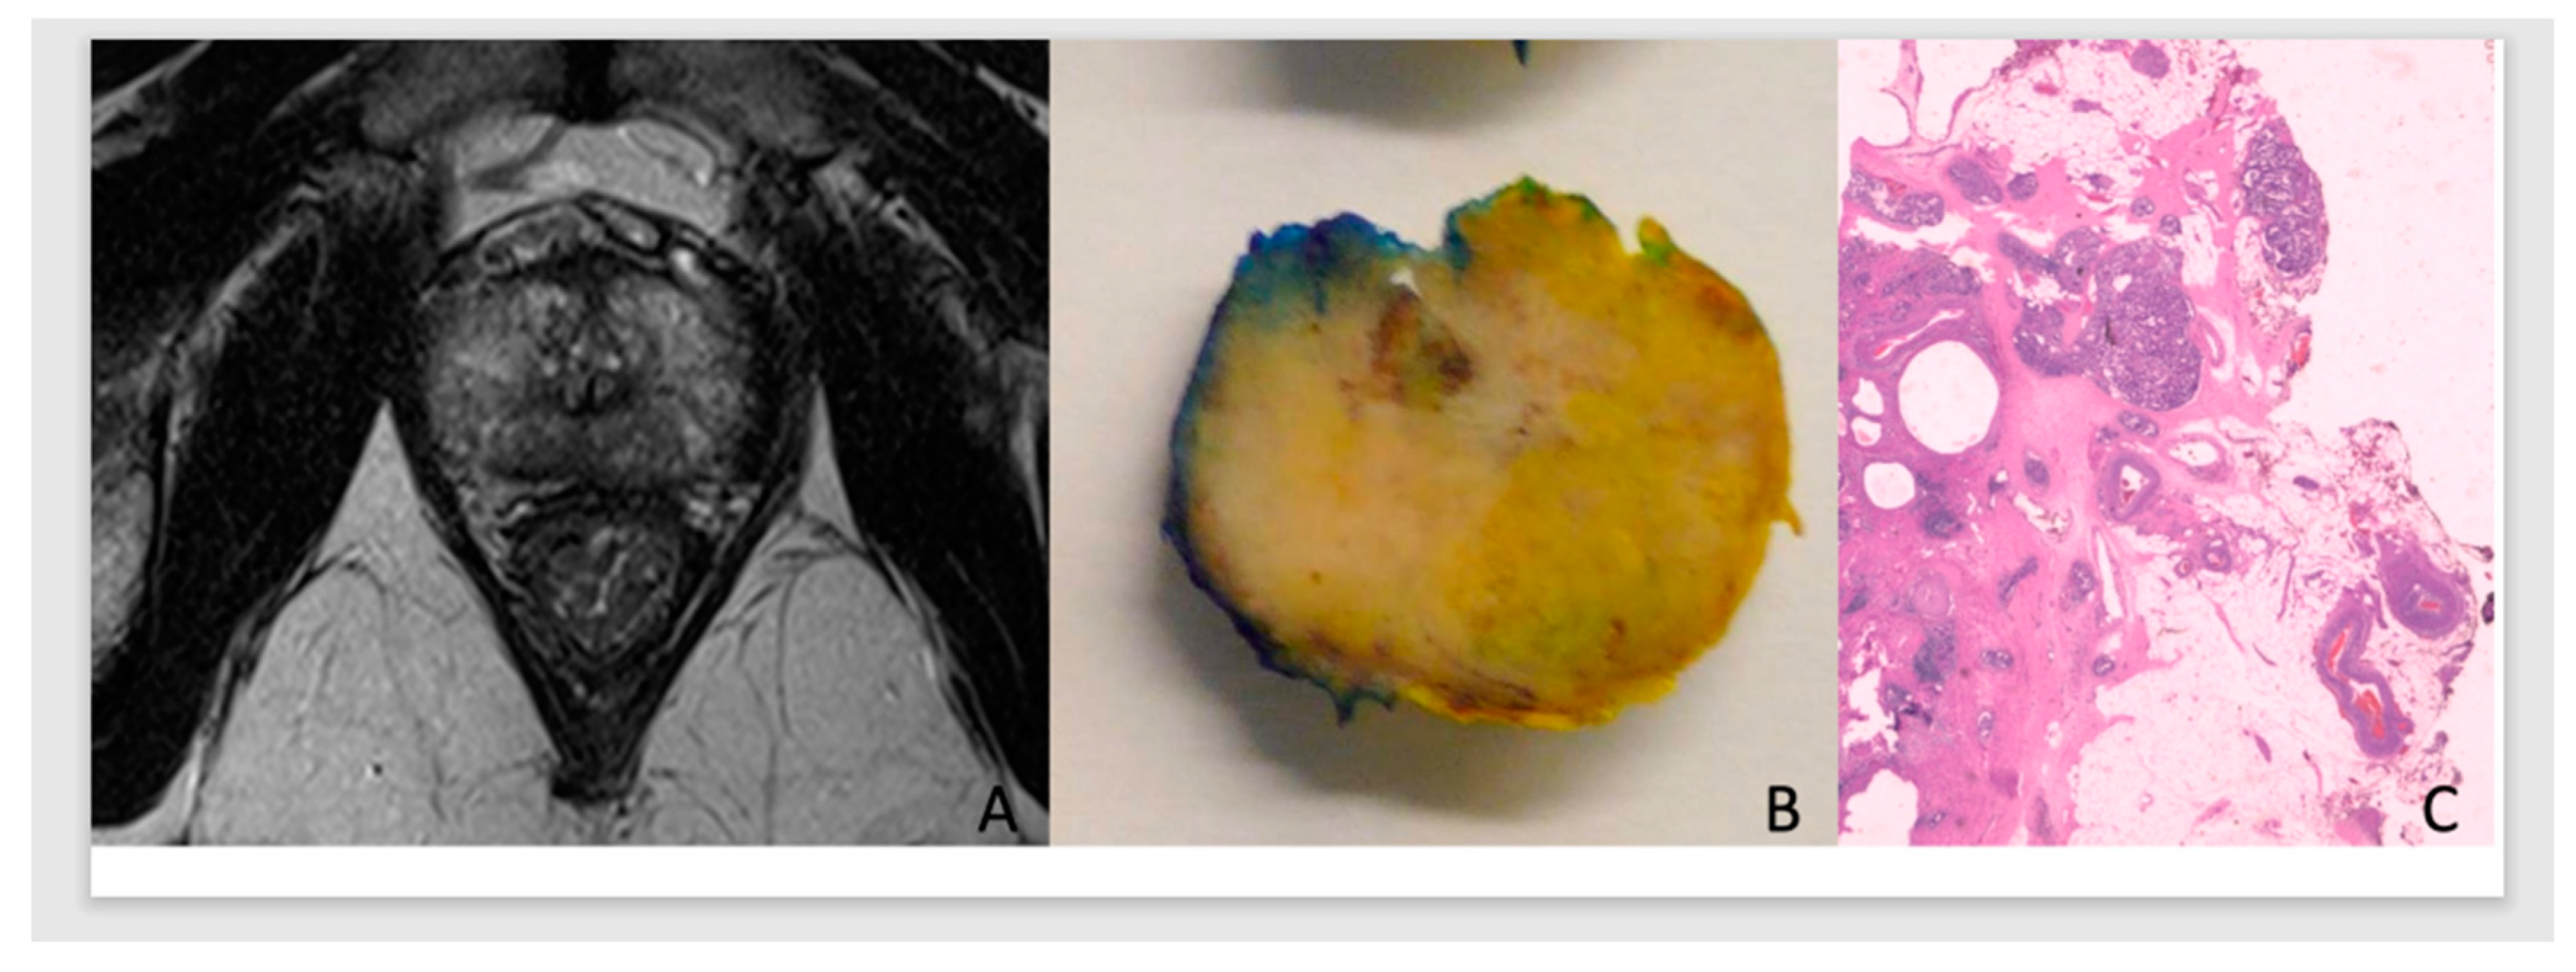

In this predictive analysis we added PCa pathological staging and surgical margins results of the prostate specimen. Tumors were classified as pECE negative (pECE−) if no tumoral cells were detected on extracapsular tissue, and pECE positive (pECE+) if a preence of a tumoral extension beyond the periphery of the prostate gland was detected (Figure 1). Positive surgical margins (PSM) refer to the presence of tumor cells beyond the inked surgical margins of the resected tumor.

Figure 1. Illustration of the MRI, anatomical and histology of PCa. ADC prostate G7(3+4) in the apex with low signal on T2WI, high TCCL, budging on MRI (a) on the right apex in the anatomic specimen (b), with pECE+ on histology (c).